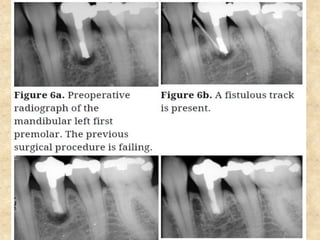

7. Repair of perforation:

• Repairing requires a material that should be biocompatible, should

withstand moisture without dissolving and should have good sealing

ability.

• MTA was used for treatment of perforation that caused by an

iatrogenic causes or complication of internal resorption.

• Procedure is done under anesthesia and rubber dam.

• After performing access opening, the canals are irrigated with NaOCl.

• Calcium hydroxide can be placed in the canal in between appointments

which will help control hemorrhage.

• Before placing MTA, calcium hydroxide should be completely removed.

• The apical portion of the canal is obturated with sectional cone

technique using gutta percha and root canal sealer.

• MTA is placed into the defect and moist cotton pellet is placed over it.

The access cavity is closed with a temporary restoration.

• The remaining portion of the canal is restored with a permanent filling

material after at least 3-4 hours.

Steps involved in the repair of perforation:

6. Obturation ofthe canal: • Mineral Trioxide Aggregate can be used to obturate the root canal of a retained primary tooth where the succedaneous permanent tooth is absent. • This technique is not recommended for obturation of primary teeth that are expected to exfoliate since it is anticipated that Mineral Trioxide Aggregate would be absorbed slowly, if at all. 7. Repair of perforation: • Repairing requires a material that should be biocompatible, should withstand moisture without dissolving and should have good sealing ability. • MTA was used for treatment of perforation that caused by an iatrogenic causes or complication of internal resorption.

• 33.

• Procedure isdone under anesthesia and rubber dam. • After performing access opening, the canals are irrigated with NaOCl. • Calcium hydroxide can be placed in the canal in between appointments which will help control hemorrhage. • Before placing MTA, calcium hydroxide should be completely removed. • The apical portion of the canal is obturated with sectional cone technique using gutta percha and root canal sealer. • MTA is placed into the defect and moist cotton pellet is placed over it. The access cavity is closed with a temporary restoration. • The remaining portion of the canal is restored with a permanent filling material after at least 3-4 hours. Steps involved in the repair of perforation: